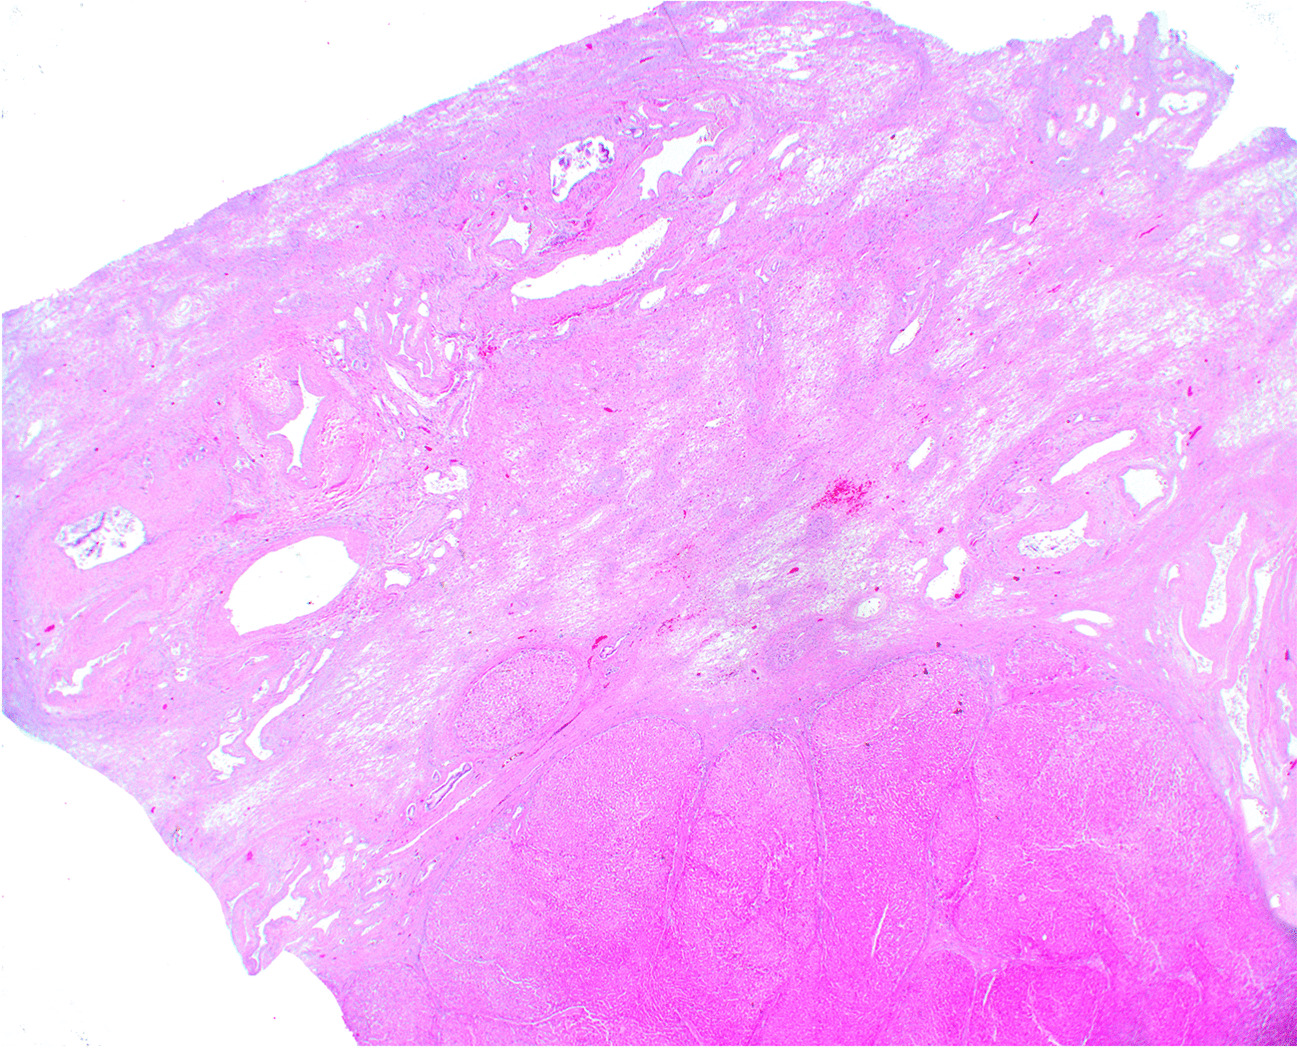

Fig. 2

Wedge resection showing segmental atrophy

Lobar and segmental atrophy of the liver (SAL) has been recognized with the routine use of computed tomography scans and ultrasound [1]. Segmental atrophy of liver is a rare condition that was first described by Singhi et al. [2] as a pseudotumor of liver manifesting as varying stages of the lesion. The pathogenesis of this lesion remains incompletely understood, but remote vascular injury and benign and malignant lesions of the liver or bile ducts might be contributing factors. Some of the described pathologic features have included the presence of abnormally thickened blood vessels throughout the lesion, involving both arteries and veins. Vascular thrombosis, fibrosis, and recanalization have all been described. The compromised perfusion of the hepatic parenchyma leads to parenchymal atrophy and loss of hepatocytes—essentially infarction over time. Early lesions are composed of collapsed hepatocytes interspersed with normal hepatocytes and bile ductular reaction with mild to moderate elastotic changes in the background. More advanced and older lesions are characterized by the presence of more elastosis, biliary cysts, and absence of bile ductular proliferation, which eventually evolves to nodular elastosis, which consists of small islands of hepatocytes within an elastic rich matrix (Figs. 1 and 2). Ruptured biliary cysts can create focal fibrosis and granulation tissue. There have been a few additional case reports and series describing the histopathologic and clinical presentations of this lesion following the initial description by Singhi et al. [2], but lack of awareness and clinicopathologic overlap of this mass-forming lesion with other hepatic lesions can create diagnostic challenges for clinicians, radiologists, and pathologists alike. A study from 2020 published in abstract form suggested an association between hepatic segmental atrophy and long-standing cardiovascular disease [3]. The aim of this study was to review the clinicopathologic features of hepatic segmental atrophy based on a large cohort of patients.

The histologic features of the lesion included elastosis and thick blood vessels in all but one of the cases (possibly a reflection of sampling error). Collapsed hepatic parenchyma with occasional small islands of atrophic hepatocytes was recognized in 44 of 45 cases. Ductular proliferation/ductular reaction was identified in 11 of 45 cases (24%). There were three cases with von-Meyenberg complexes. None of the cases showed findings of focal nodular hyperplasia or porto-sinusoidal vascular disease.